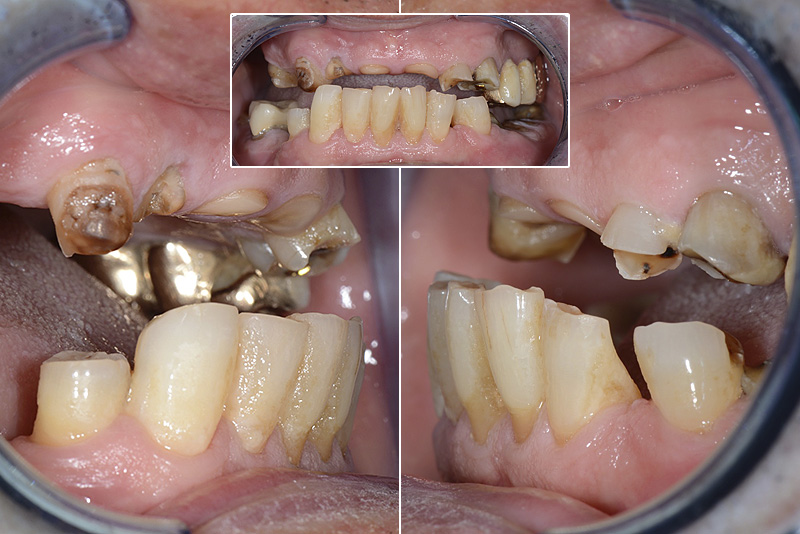

PREMESSA: in seguito all’estrazione dell’incisivo laterale superiore di destra, resasi necessaria per cause batteriche, si decide di affrontare il caso con il posizionamento di un impianto in sostituzione dell’elemento mancante dopo guarigione del sito infetto. Con tecniche rigenerative sia dei tessuti ossei mancanti a causa dell’infezione pregressa, sia dei tessuti gengivali che appaiono inizialmente troppo spostati in alto, si ripristina una corretta morfologia delle parabole (contorni) gengivali e delle papille interdentali (triangoli di gengiva tra due denti vicini).